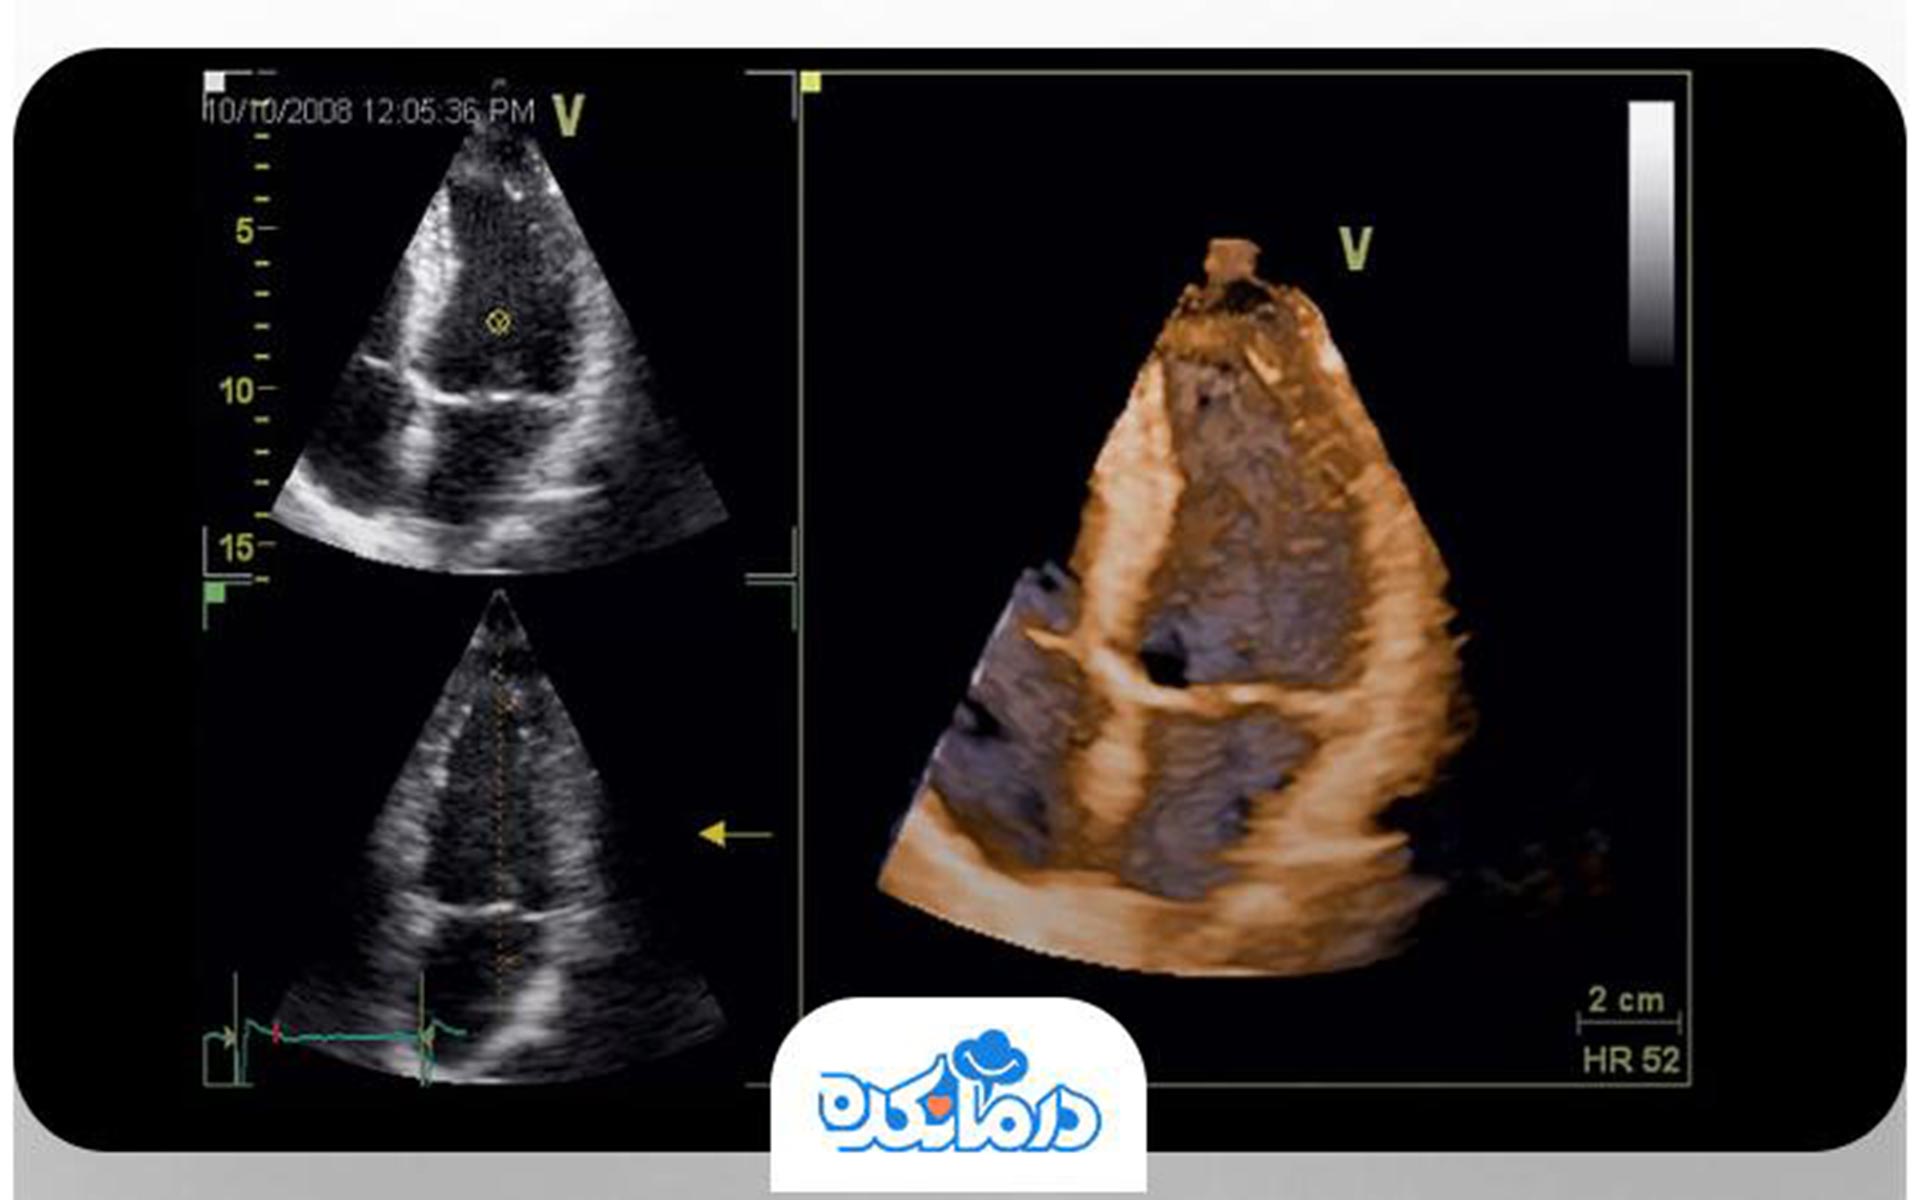

اکوکاردیوگرافی سهبعدی

در این تکنیک دستگاه اکوکاردیوگرام تصاویر سهبعدی از عضله قلب در اختیار پزشک قرار میدهد. تصاویر سهبعدی جزییات بیشتری از وضعیت قلب را نشان میدهند. برای انجام آن به آمادگی خاصی نیاز ندارید و در همان روز میتوانید به فعالیتهای روزمره خود بپردازید.